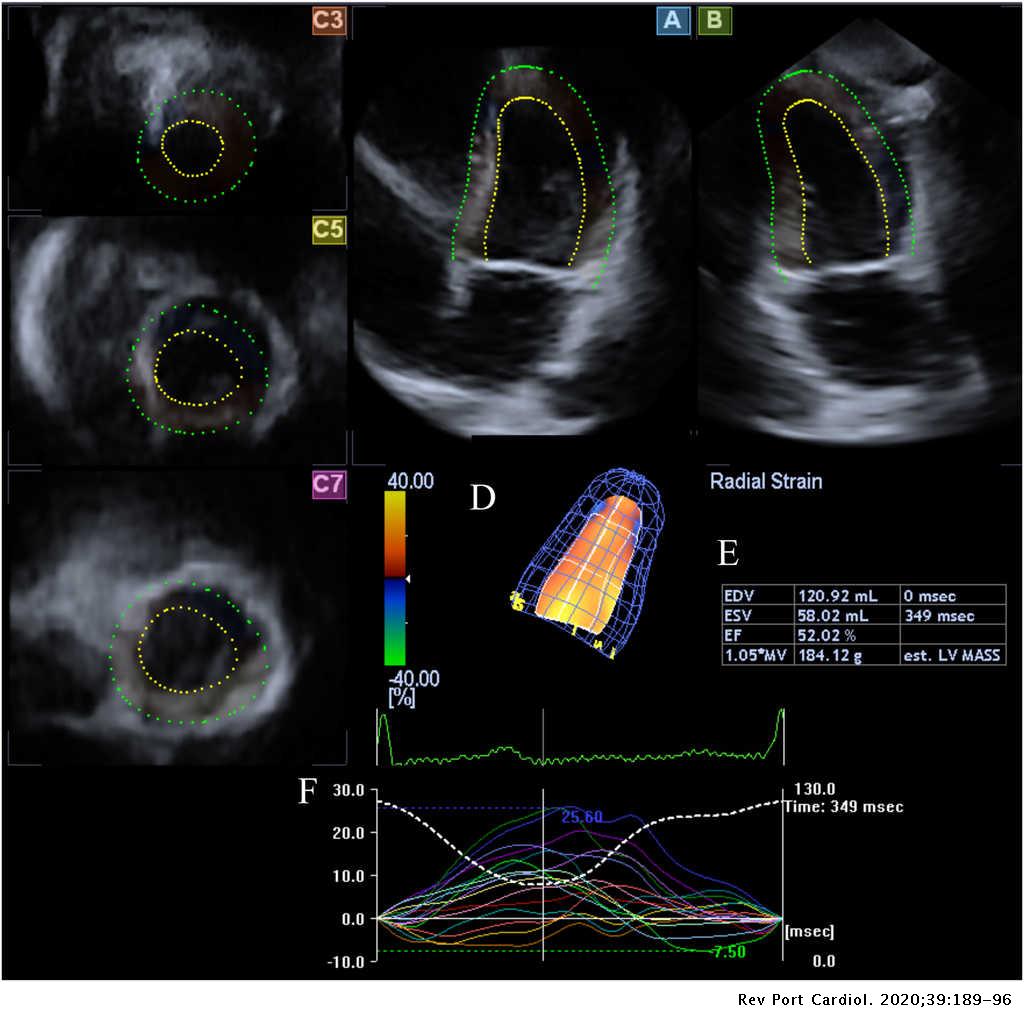

Active Acromegaly Is Associated With Enhanced Left Ventricular Contractility Results From The Three Dimensional Speckle Tracking Echocardiographic Magyar Path Study Revista Portuguesa De Cardiologia